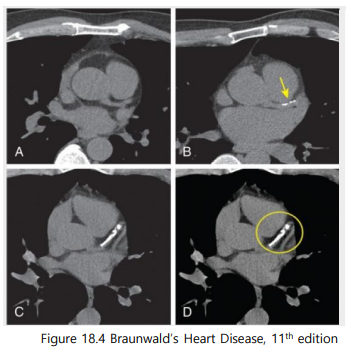

요즘 혈액순환도 안 좋고 나이도 드는데…혈관이 걱정이에요.최근 언론을 통해 다양한 건강 관련 보도가 나오면서 본인의 혈관동맥경화를 걱정하는 분들이 많이 계십니다. ^^ 내 혈관의 동맥경화는 어떻게 알 수 있습니까.대표적인 검사를 소개하자면 ① 심장혈관 CT(아래 그림) ② 경동맥 초음파(아래 그림) ③ 혈관경직도검사(ABI, PWV)에서는 검사가 있습니다.

심장칼슘 CT(coronary calcium score)가 무엇입니까?심장혈관에 칼슘이 얼마나 쌓여 있는가는 보는 검사에서 CT상 하얗게 보이는 부분입니다.(심장조영술과는 다릅니다. 심장혈관조영술은 조영제를 넣어 혈관을 직접 보는 시술로 보다 정확하지만 고위험 시술입니다.)

심장혈관조영술과는 다른 검사주의 CA Cscore (Agatstonscale) 뜻0 혈관에 칼슘침착이 없음1-10lowrisk 심장혈관질환 위험도 10% 미만 11-99 약간의 혈관칼슘침착 100-399 중등도 혈관칼슘침착 400-999 심각한 혈관칼슘침착 1000+1년 내에 심장혈관질환 발생확률 25% 이상 Q. AHA/ACC cholesterol guideline (2018)

40-75세 사이 LD Lcholesterol이 70-190인 경우 (or ASCVD 77.5-<20% Intermediaterisk의 경우) 심장칼슘 CT를 촬영하여 치료방향 설정에 도움을 줍니다.

- CAC=0→Nostatinunless DM, Smoking, FHx: “Power ofzero”: 약을 사용하지 않고 볼 수 있다.2) CAC=1-99 (Mildcalcium deposit)→statin약을 먹는 것이 좋다 3) CAC100100 and / or 7575th percentile → statin약을 빨리 사용하라

- 최근 다양한 권고안에서는(Circulation. 2019; 140: e596 – e646/European Heart Journal (2021) 42,32273337) 심장칼슘 CT를 경동맥 초음파에서 권장하는 경향이 관찰됩니다.